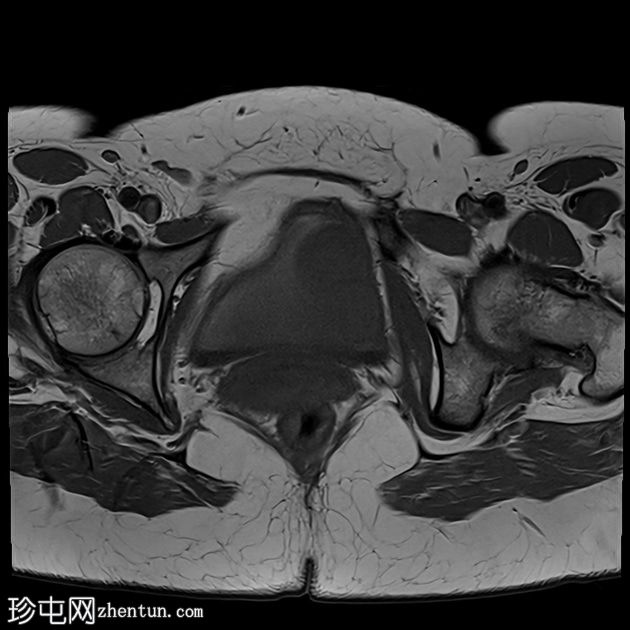

轴位

T2加权像

可见膀胱左侧壁有一边界清晰的T2低信号实

性病

灶,无扩散受限,均匀强化。未见膀胱周围侵犯或肾积水。

子宫底部前壁可见一小肌瘤。双侧卵巢可见无强化囊肿。盆腔及腹股沟未见异常淋巴结肿大。

这是一例经组织学证实的膀胱平滑肌瘤病例。